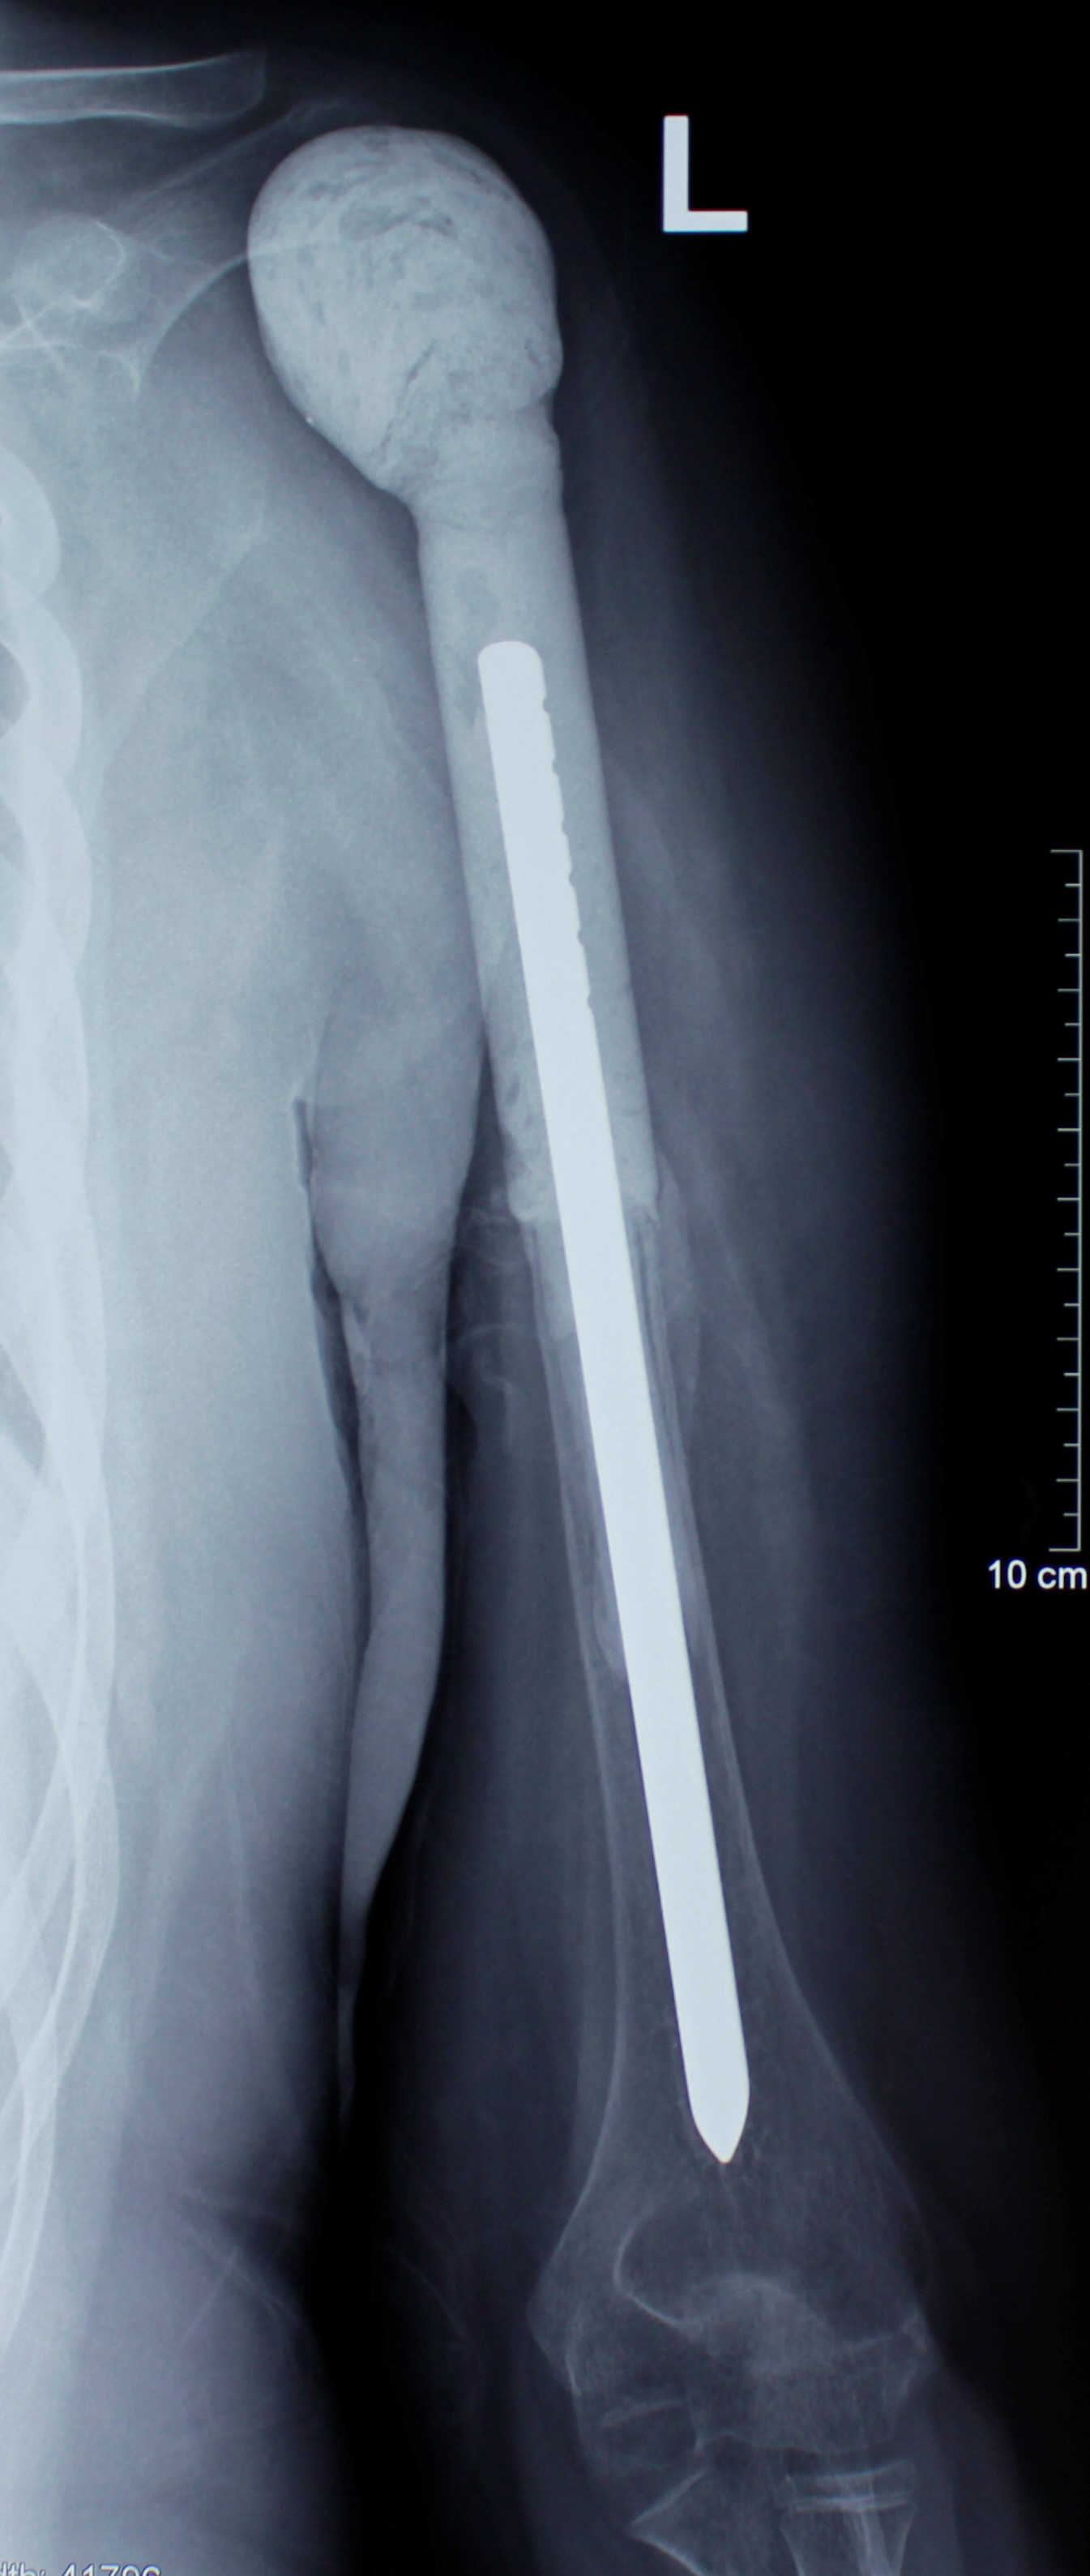

2. Բժշկական տարբեր կենտրոններում հետազոտվելուց հետո՝ 17-ամյա պատանին դիմել է «Նաիրի» ԲԿ։ Համապատասխան հետազոտություններ անցնելուց հետո՝ բուժառուի մոտ հայտնաբերվել է ոլոքի օստեոսարկոմա (ոսկրային քաղցկեղ): Նախավիրահատական բուժում ՝ քիմիոթերապիա, ստանալուց հետո՝ «Նաիրի» ԲԿ ում կատարվել է օրգանապահպան վիրահատություն : Հեռացվել են ծնկահոդն ու ոլոքի վերին երորդականը: Առաջացած դեֆորմացիան շտկել է Եվրոպայից պատվիրված էդոպրոթեզով, որը հնարավորություն է տվել պահպանել վերջույթի գործառույթը՝ քայլել, վազել և այլն։ Հետվիրահատական շրջանում բուժառուն ստացել է քիմիոթերապիա։ Այժմ գտնվում է բժիշկների հսկողության ներքո։

Վիրահատությունից հետո